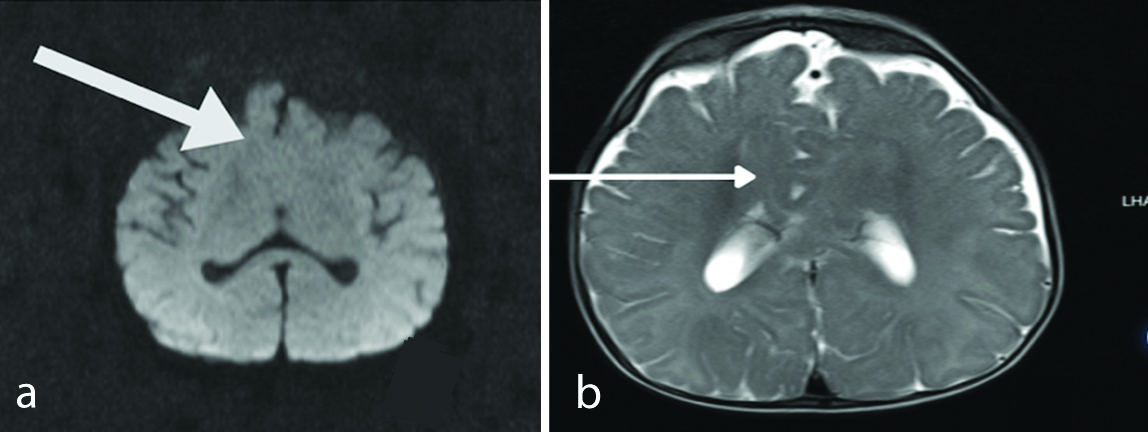

An MRI scan conducted at six months revealed fusion of the anteroinferior aspect of the frontal lobe across the midline. The frontal horns of the lateral ventricles and the septum pellucidum were absent. Additionally, the anterior aspect of the third ventricle was partially obliterated, and there was evidence of dysgenesis of the corpus callosum. The MRI findings were suggestive of semilobar holoprosencephaly [Table/Fig-2a,b].

a) The anteroinferior portion of the frontal lobe is fused in the middle. Dysgenesis of the corpus callosum; b) The third ventricle is partially obliterated.